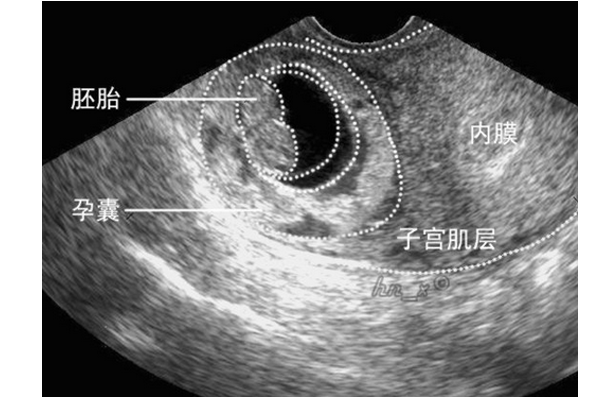

孕囊在子宫位置图片

孕囊:子宫中的受精卵通过4周半左右的发育,慢慢形成孕囊,刚成形时只有

当受精卵植入到子宫内膜后,就会逐渐成长为孕囊,是被羊膜,血管网等

34 × 15 mm,胚芽长 10 mm,见心管搏动,孕囊位置偏下,靠近子宫峡部